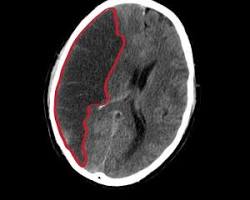

뇌혈관연축은 뇌동맥류 파열 후 혈관이 수축하여 뇌혈류가 감소하는 질환입니다. 이로 인해 다양한 합병증이 발생할 수 있습니다.

• 뇌경색: 뇌혈관이 막히면서 뇌세포가 죽는 질환입니다. 뇌경색이 발생하면 마비, 감각 이상, 언어 장애 등 다양한 신경학적 증상이 나타날 수 있습니다.

• 뇌부종: 뇌세포에 산소와 영양분 공급이 부족해지면 뇌세포가 부어오르는 현상입니다. 뇌부종은 뇌압을 상승시켜 생명을 위협할 수 있습니다.

• 수두증: 뇌척수액이 정상적으로 순환되지 않아 뇌실이 확장되는 질환입니다. 두통, 구토, 의식 저하 등의 증상이 나타날 수 있습니다.